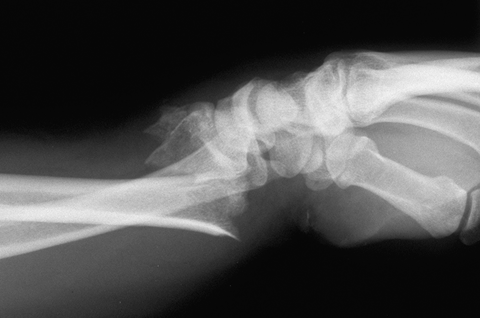

Case 5 Preop